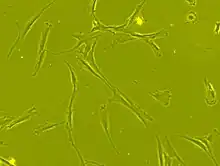

Human bone marrow derived mesenchymal stem cells seen under phase contrast microscope (63 x magnification)

Stem cell transplantation is an important avenue for SCI research: the goal is to replace lost spinal cord cells, allow reconnection in broken neural circuits by regrowing axons, and to create an environment in the tissues that is favorable to growth.[76] A key avenue of SCI research is research on stem cells, which can differentiate into other types of cells—including those lost after SCI.[76] Types of cells being researched for use in SCI include embryonic stem cells, neural stem cells, mesenchymal stem cells, olfactory ensheathing cells, Schwann cells, activated macrophages, and induced pluripotent stem cells.[162] Hundreds of stem cell studies have been done in humans, with promising but inconclusive results.[149] An ongoing Phase 2 trial in 2016 presented data[163] showing that after 90 days, 2 out of 4 subjects had already improved two motor levels and had thus already achieved its endpoint of 2/5 patients improving two levels within 6–12 months. Six-month data is expected in January 2017.[164]